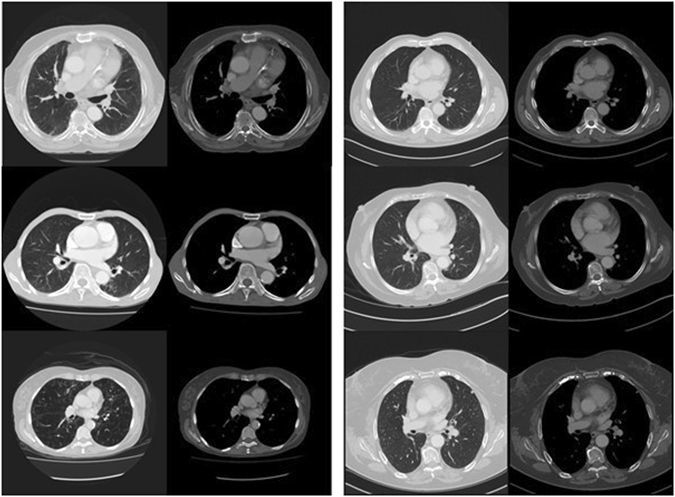

阿德莱德大学研究人员刚刚在《自然》杂志上发表的一篇论文展示了他们的最新成果。该系统通过一个深度学习系统,为48例患者的CT扫描照片进行了“未来5年是否会死亡”的诊断预测。预测精度为69%,与人类医生的准确度相似。

研究人员之一的流行病专家莱尔·帕尔默在接受采访时解释说,这些CT扫描照片中往往隐藏着一些即便是医学专家也无法破译和解读的某些躯体特征,而深度学习能够从中找出哪怕最微小的异常。